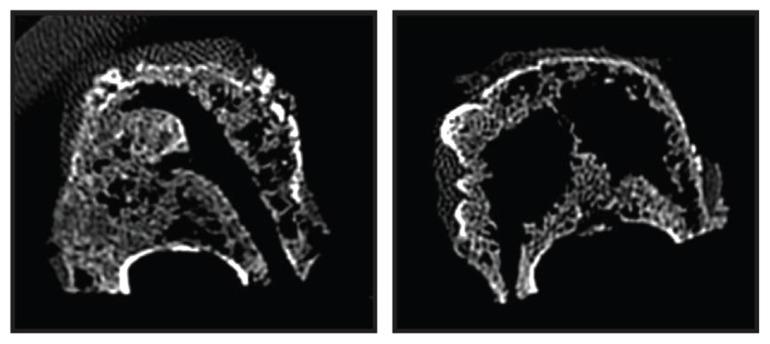

This ex vivo biomechanical pilot study utilized 16 osteoporotic cadaveric vertebral bodies in a standardized fracture model to compare unipedicular RF-TVA (n = 8) to bipedicular BK (n = 8). Four specimens from each group were tested in loaded and unloaded conditions. All specimens were imaged, assessed for height restoration, and sectioned to observe PMMA distribution. A subset of specimens underwent computed tomography scanning to assess cavity creation and trabecular architecture prior to cement delivery.

Anterior height restoration was greater with RF-TVA (median: 84%, interquartile range: 62%-95%) compared to BK (median: 69%, interquartile range: 60%-81%), although the difference did not achieve statistical significance (P = 0.16). Anterior height restoration was numerically greater under loaded (median: 70% versus 66%) and unloaded (median: 94% versus 77%) conditions with RF-TVA versus BK. RF-TVA produced more discrete cavities and less native trabecular destruction compared to marked trabecular destruction observed with BK. RF-TVA consistently showed a well-identified focal area of PMMA with an extensive peripheral zone of PMMA interdigitation, providing mechanical interlock into the adjacent intact trabecular matrix. In contrast, BK yielded little evidence of PMMA interdigitation beyond the boundaries created by the balloon tamp due to the crushed trabecular bone peripherally.

本体外生物力学初步研究使用 16 个骨质疏松性尸体椎体在标准化骨折模型中比较单通道 RF-TVA(n=8)与双通道 BK(n=8)。每组的 4 个标本分别在加载和未加载条件下进行测试。所有标本均进行成像、评估高度恢复,并进行切片观察 PMMA 分布。部分标本在输送水泥前进行计算机断层扫描以评估空腔形成和小梁结构。

RF-TVA 的前柱高度恢复更高(中位数:84%,四分位距:62%-95%),与 BK(中位数:69%,四分位距:60%-81%)相比,差异虽无统计学意义(P=0.16)。RF-TVA 在加载(中位数:70%对 66%)和未加载(中位数:94%对 77%)条件下的前柱高度恢复均大于 BK。与 BK 观察到的明显小梁破坏相比,RF-TVA 产生的空腔更离散,对原生小梁的破坏更少。RF-TVA 始终显示出 PMMA 的明确焦点区域,以及 PMMA 交织的广泛外围区域,为相邻完整小梁基质提供机械互锁。相比之下,由于周围小梁骨粉碎,BK 产生的 PMMA 交织痕迹很少超出球囊扩张所形成的边界。